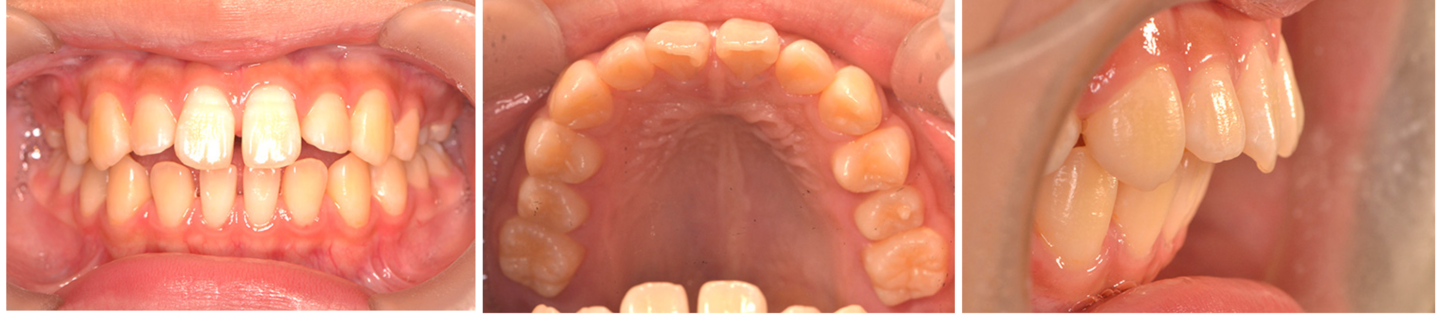

17歳女性 歯列不正 上のみ抜歯

治療前の写真

治療前

治療後の写真

治療後